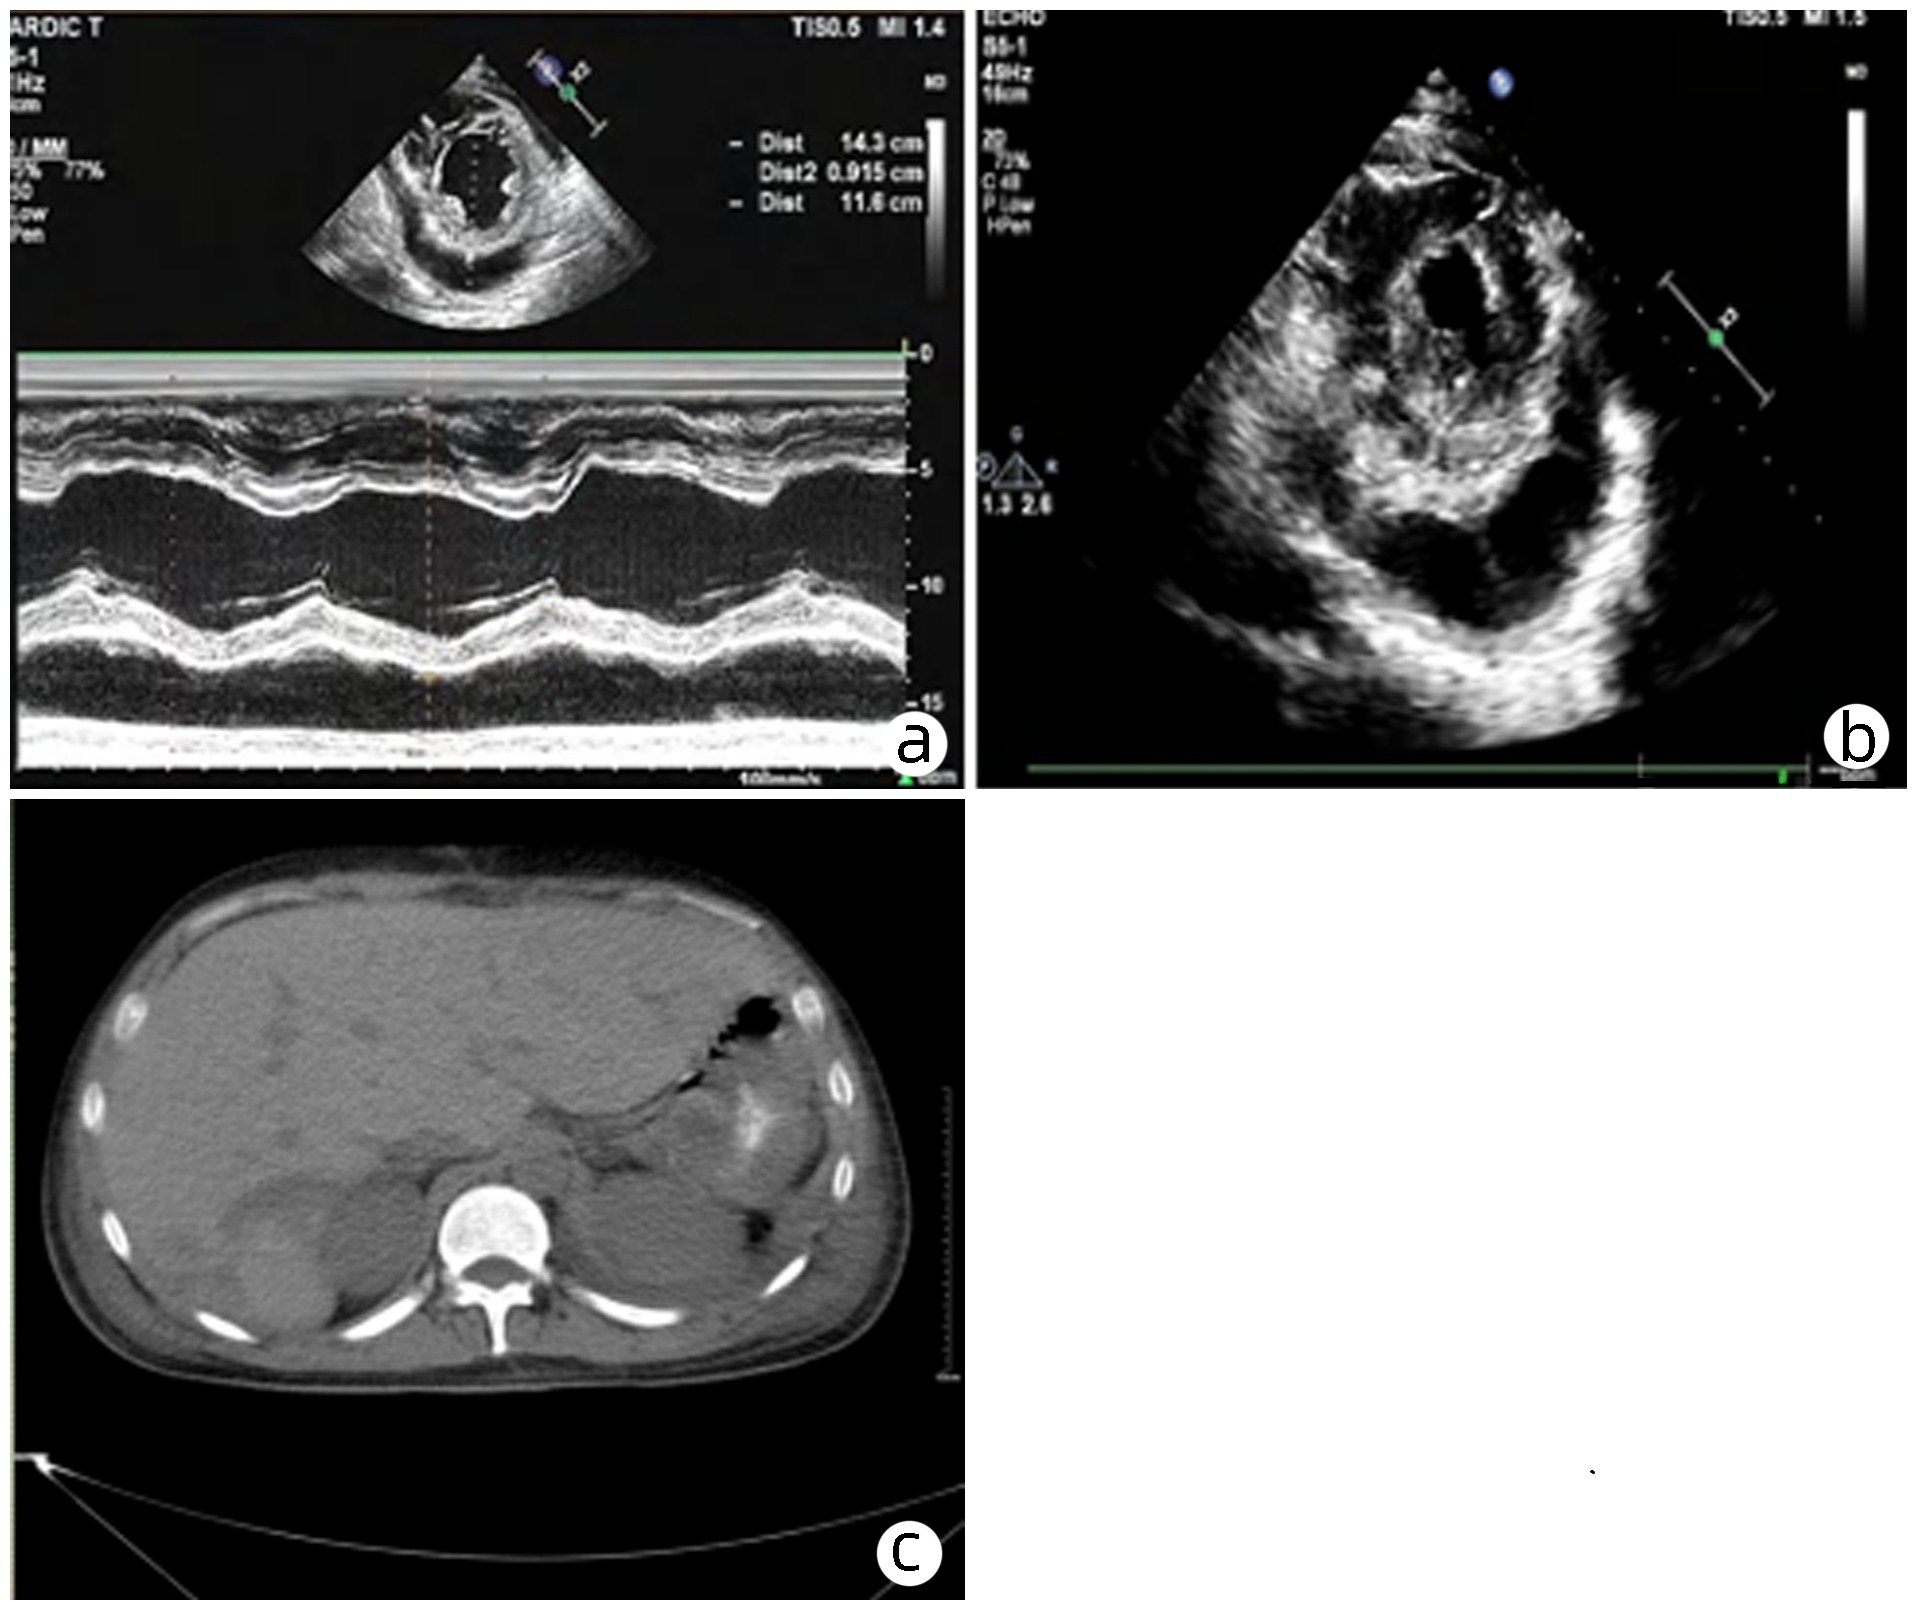

Sepsis with spontaneous splenic rupture and hemorrhage: A case report

Zhou LIU, Wenfang XIA, Liying ZHAN, Xiaoyu FANG, Liang ZHANG, Na ZHAN, Rong YU, Li HANG, Lei ZHU

2023, 39(8): 1926-1931. DOI: 10.3969/j.issn.1001-5256.2023.08.024

Abstract(1289) HTML (293) PDF (4249KB)(98)

Abstract:

Severe infections due to sepsis often result in multi-organ insufficiency, such as cardiac insufficiency, renal insufficiency, hypohepatia, septic encephalopathy, coagulation dysfunction etc. Severe infections not only cause inflammatory storm, but also induce spleen abscess, and even combined with spontaneous splenic rupture hemorrhage. Spontaneous splenic rupture has an insidious onset, usually without a history of trauma, and is easily missed diagnosis. In this case, the patient with sepsis had sudden onset of abdominal pain and progressive decrease in hematocrit, thus the abdominal CT was immediately performed. The perisplenic mixed high-density shadow indicated splenic hemorrhage. After consultation with the department of hepatobiliary surgery, emergency dissection was performed. Splenic hematoma and laceration were found during the operation, thus total splenectomy was conducted. Pathological indicated chronic inflammatory cell infiltration of spleen, spleen abscess with bleeding. After operation, the patient's hematocrit was stable, abdominal pain improved significantly, and he was discharged from hospital after systematic therapy.